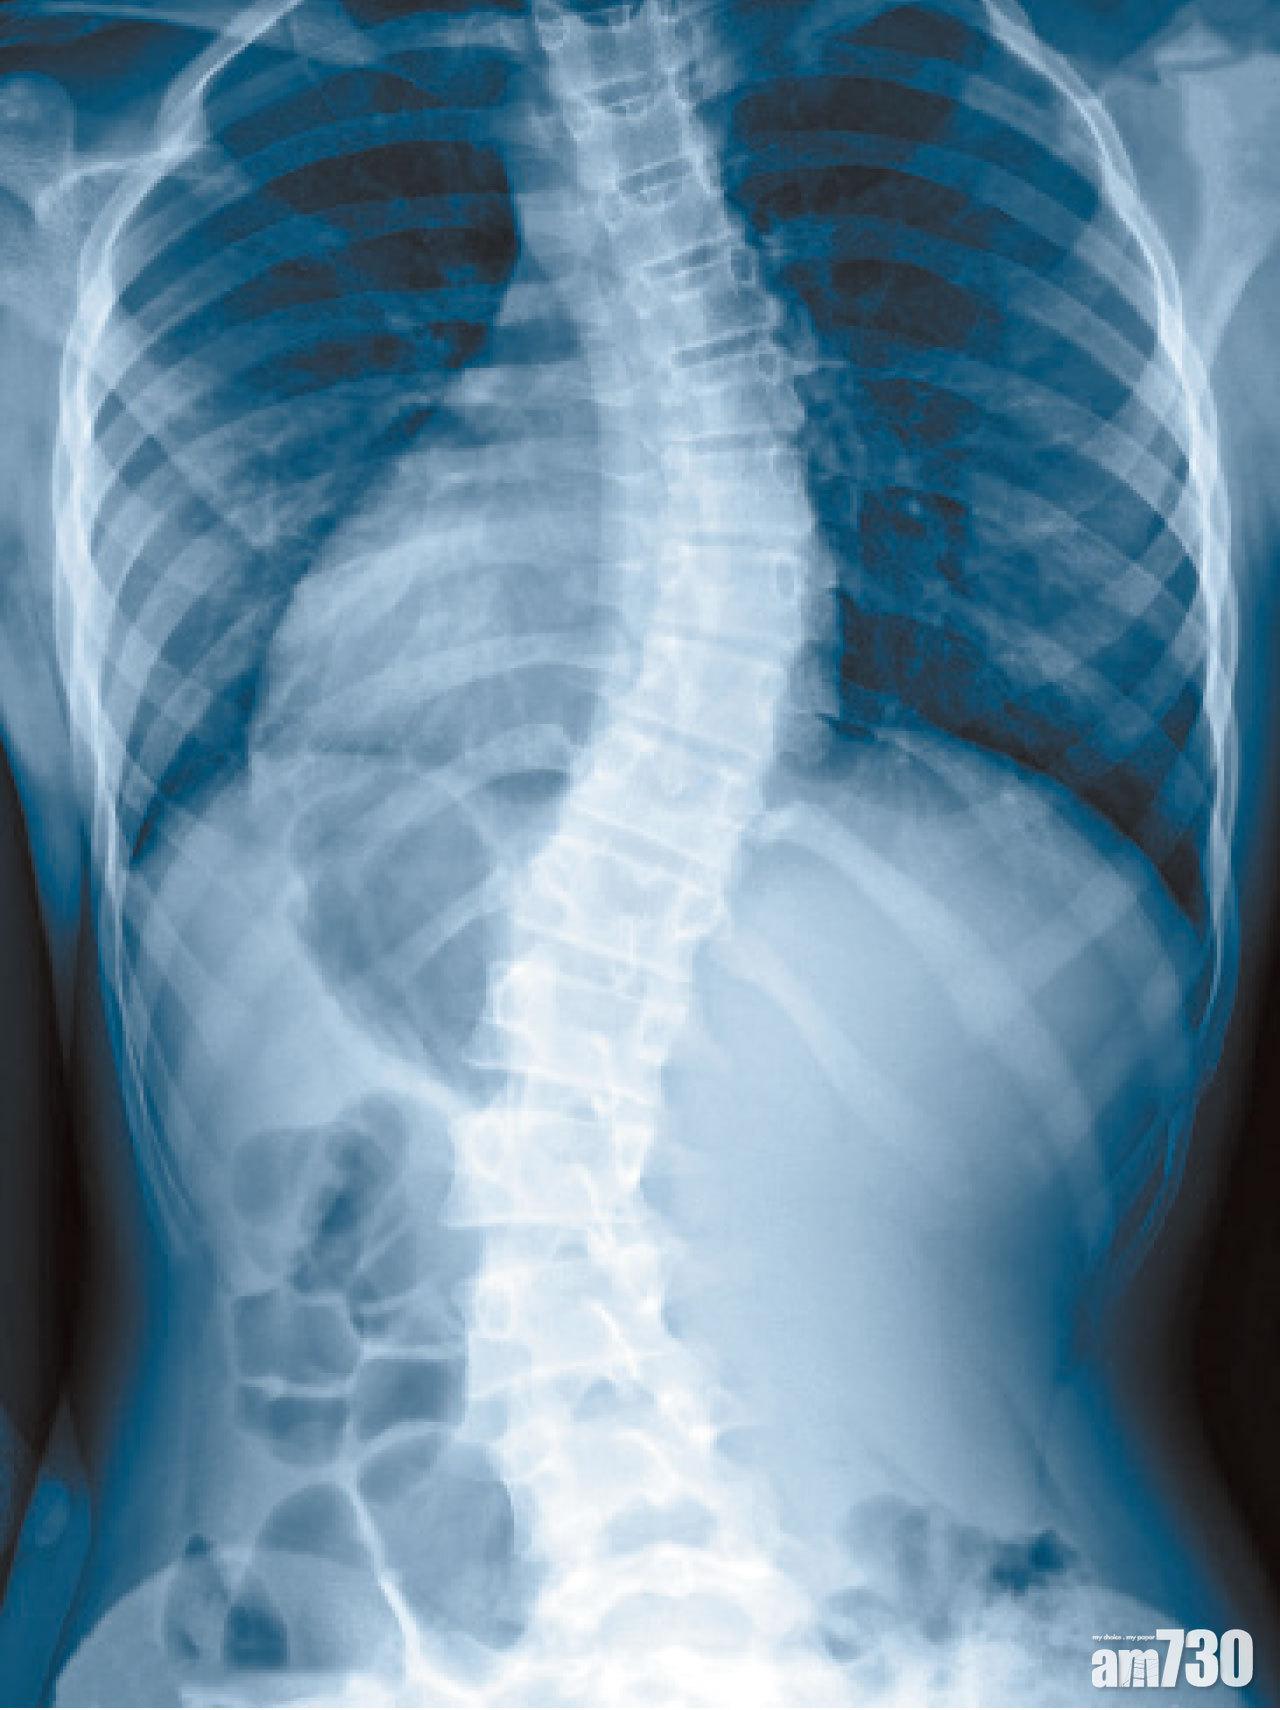

脊柱側彎是指脊柱向左或向右彎曲,呈現C形或S形,或會導致肩背不平、盆骨傾斜等身體不平衡。一般成年人過了發育期,對體形比例或未有像父母對孩子般那麼著緊,所以許多時候,往往到身體出現問題,如下腰背痛楚、腳痹、活動能力下降等去求診,才發現跟脊柱側彎有關。

脊柱側彎可分為兩種,第一種是成年原發性脊柱側彎,較常見於40歲至60歲、身體開始出現退化的人士身上,多發於下腰椎部位。第二種是童年時曾患有原發性脊柱側彎,年長後才變成退化性脊柱側彎。此病除影響外觀外,還會帶來腰骨痛及骨刺。如果骨刺生長在椎管內,會壓住神經,導致腳痹乏力,情況嚴重者,甚至會大小便失禁。由於患者肌肉需要用的力量會比正常人多,走幾步路也會覺疲累。